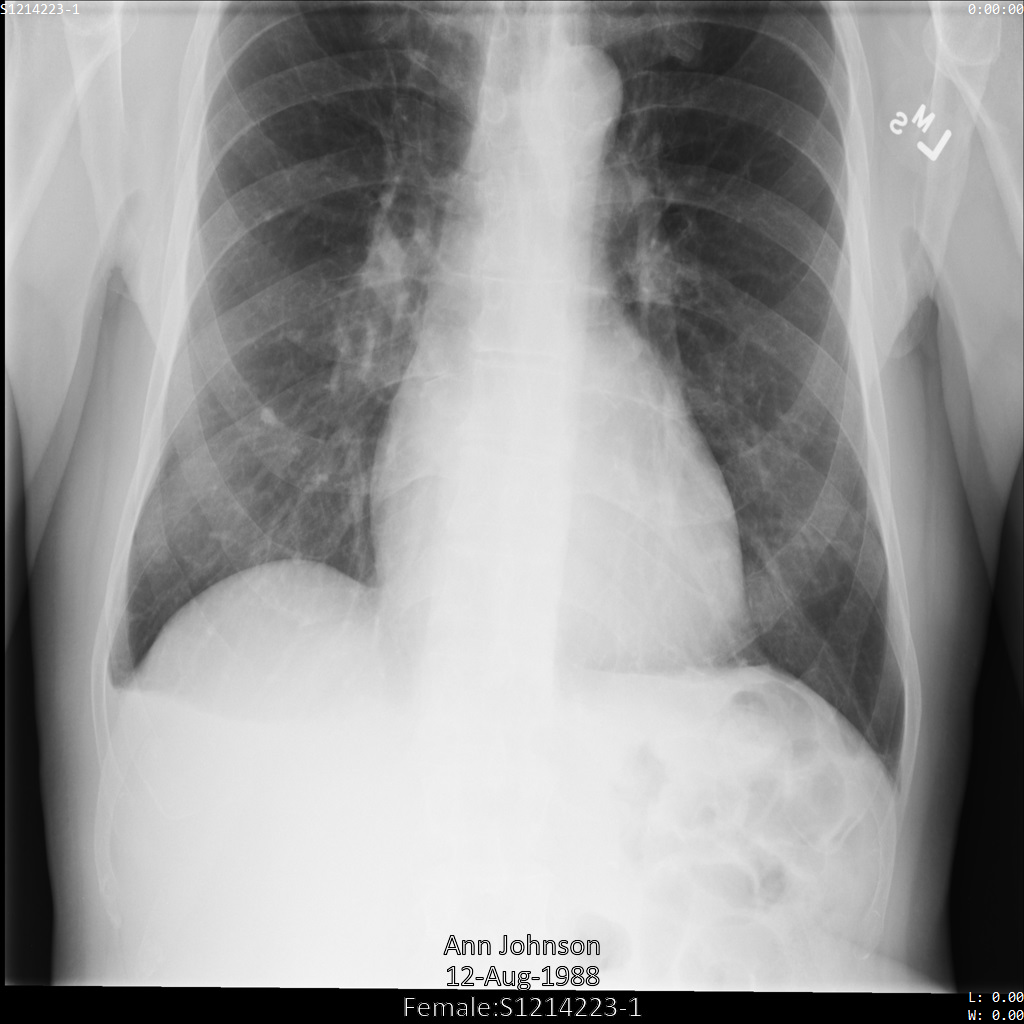

Chacune des sections suivantes fournit des exemples d'anonymisation de données DICOM à l'aide de différentes méthodes. Une sortie de l'image anonymisée est fournie avec chaque échantillon. Chaque exemple utilise l'image d'origine suivante comme entrée :

Vous pouvez comparer l'image de sortie de chaque opération d'anonymisation à cette image d'origine pour voir les effets de l'opération.

Une fois l'image envoyée à l'API Cloud Healthcare, elle apparaît comme suit. À l'exception des balises fournies dans la liste de suppression, seul PatientBirthDate est supprimé dans l'image, car il s'agit de la seule balise de la liste de suppressions qui correspond aux métadonnées visibles dans l'image.

Bien que le PatientBirthDate dans l'angle supérieur de l'image ait été masqué conformément à la configuration de la liste removelist, les données de santé protégées incrustées en bas de l'image sont conservées. Pour supprimer également le texte incrusté, consultez la section Masquer le texte incrusté dans les images.